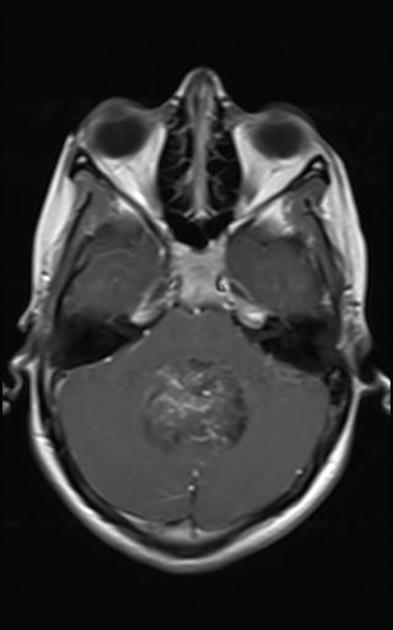

Axial T2Sagital FLAIR

Axial T1Axial T1 GadAxial T1 Gad/fat sat

For a detailed discussion of ependymoma imaging see Radiopedia for an excellent discussion on ependymoma imaging by Weerikoddy and Galliard.

MRI Brain

Careful examination of the entire neuraxis is required to assess for the presence of CSF seeding.